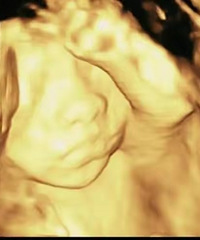

我花钱拍的彩超“一塌糊涂”,还没有免费彩超照得清楚

1个月前 收录

阅读:2.7万回复:80